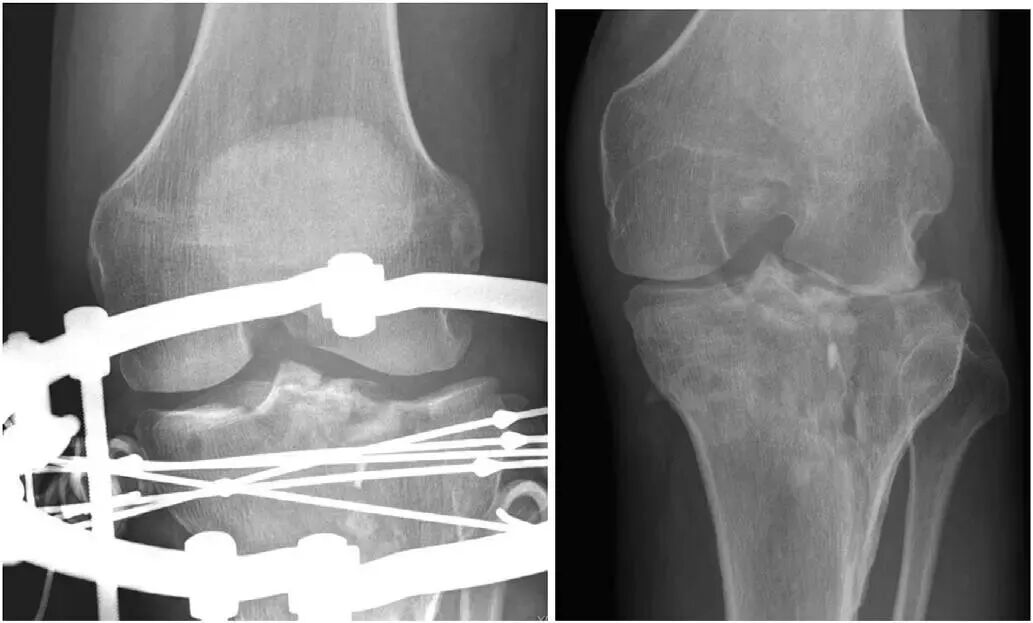

胫骨平台骨折术后力线异常会改变胫骨平台 的载荷分布和应力传导,可能对膝关节短期功能影响不大,但长期容易继发PTOA,甚至需要行膝关节置换术治疗。

术后膝关节冠状面或矢状面力线异常(≥5°)是导致患者行膝关节置换的独立危险因素。

维持膝关节稳定性对于胫骨平台骨折复位至关重要;特别是对于关节面严重粉碎塌陷的骨折,很难实现关节面的解剖复位,这时最重要的目标莫过于恢复膝关节的稳定性,允许患者术后在相对无痛的情况下尽早开始康复训练, 随着时间的推移,患者膝关节可能会因为残留的关节面不平整而出现PTOA,但这一般是数年或数十年以后的并发症;若骨折术后膝关节不稳定,患者会因难以开始康复锻炼进而导致膝关节疼痛、活动受限和打软腿等。

胫骨平台骨折术后膝关节不稳定,既可能因为关节面复位不良使相应关节间隙增大所致,也可能因为骨折合并膝关节韧带断裂或韧带止点撕脱性骨折引起的韧带性不稳定所致。